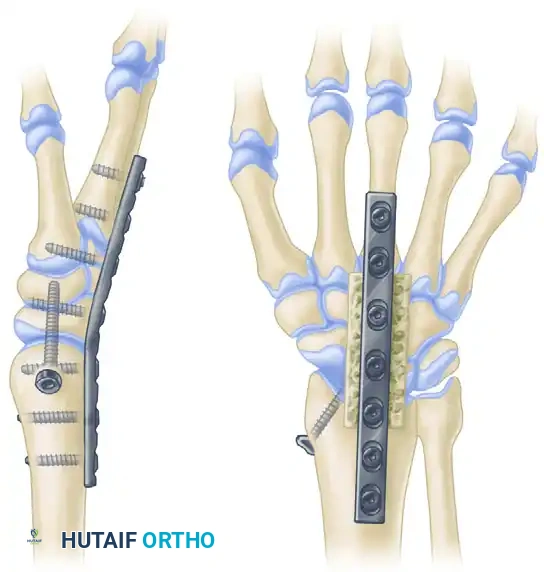

SURGICAL TECHNIQUE 2: AO/ASIF DYNAMIC COMPRESSION PLATING

The modern standard of care for wrist arthrodesis utilizes rigid internal fixation via dynamic compression plating. This technique, championed by the AO Foundation, provides superior biomechanical stability, significantly higher union rates, and eliminates the morbidity associated with prolonged cast immobilization.

Advantages of the AO/ASIF Technique

- Immediate Stability: Allows for early mobilization of the digits, reducing postoperative stiffness.

- High Union Rates: Dynamic compression across the radiocarpal joint promotes primary bone healing.

- Anatomic Contouring: Modern pre-contoured wrist fusion plates are manufactured with a built-in 10 to 15-degree dorsal bend, ensuring optimal functional positioning without the need for intraoperative plate bending.

Step-by-Step Plating Technique

- Exposure: A straight dorsal longitudinal incision is made in line with Lister's tubercle, extending from the distal third of the radius to the base of the third metacarpal.

- Compartment Management: The third dorsal compartment is opened, and the Extensor Pollicis Longus (EPL) is mobilized and retracted radially. The fourth compartment (EDC) is elevated subperiosteally and retracted ulnarly. Lister's tubercle is flattened using a rongeur or burr to create a flat bed for the plate.

- Joint Preparation: The radiocarpal joint (scaphoid lunate, radius), midcarpal joint (capitate), and the third carpometacarpal joint are decorticated. Cancellous bone graft (autograft from the distal radius or allograft) is packed into the interstices.

- Plate Application: A specialized 3.5mm/2.7mm pre-contoured wrist fusion plate is applied dorsally.

- The distal end of the plate is secured to the diaphysis of the third metacarpal using 2.7mm screws.

- The proximal end is secured to the distal radius using 3.5mm screws.

- A dedicated lag screw is often passed through the plate, traversing the radius and compressing directly into the capitate to ensure rigid radiocarpal coaptation.

FIGURE 69-81: Arthrodesis of the wrist utilizing a pre-contoured dynamic compression plate. Note the central lag screw providing direct compression across the radiocarpal articulation, and the built-in dorsal extension angle optimizing grip biomechanics.

Clinical Pearl: Third Metacarpal Fixation

When securing the plate to the third metacarpal, ensure the screws are bicortical but do not protrude excessively into the volar soft tissues, as this can cause flexor tendon irritation or rupture.